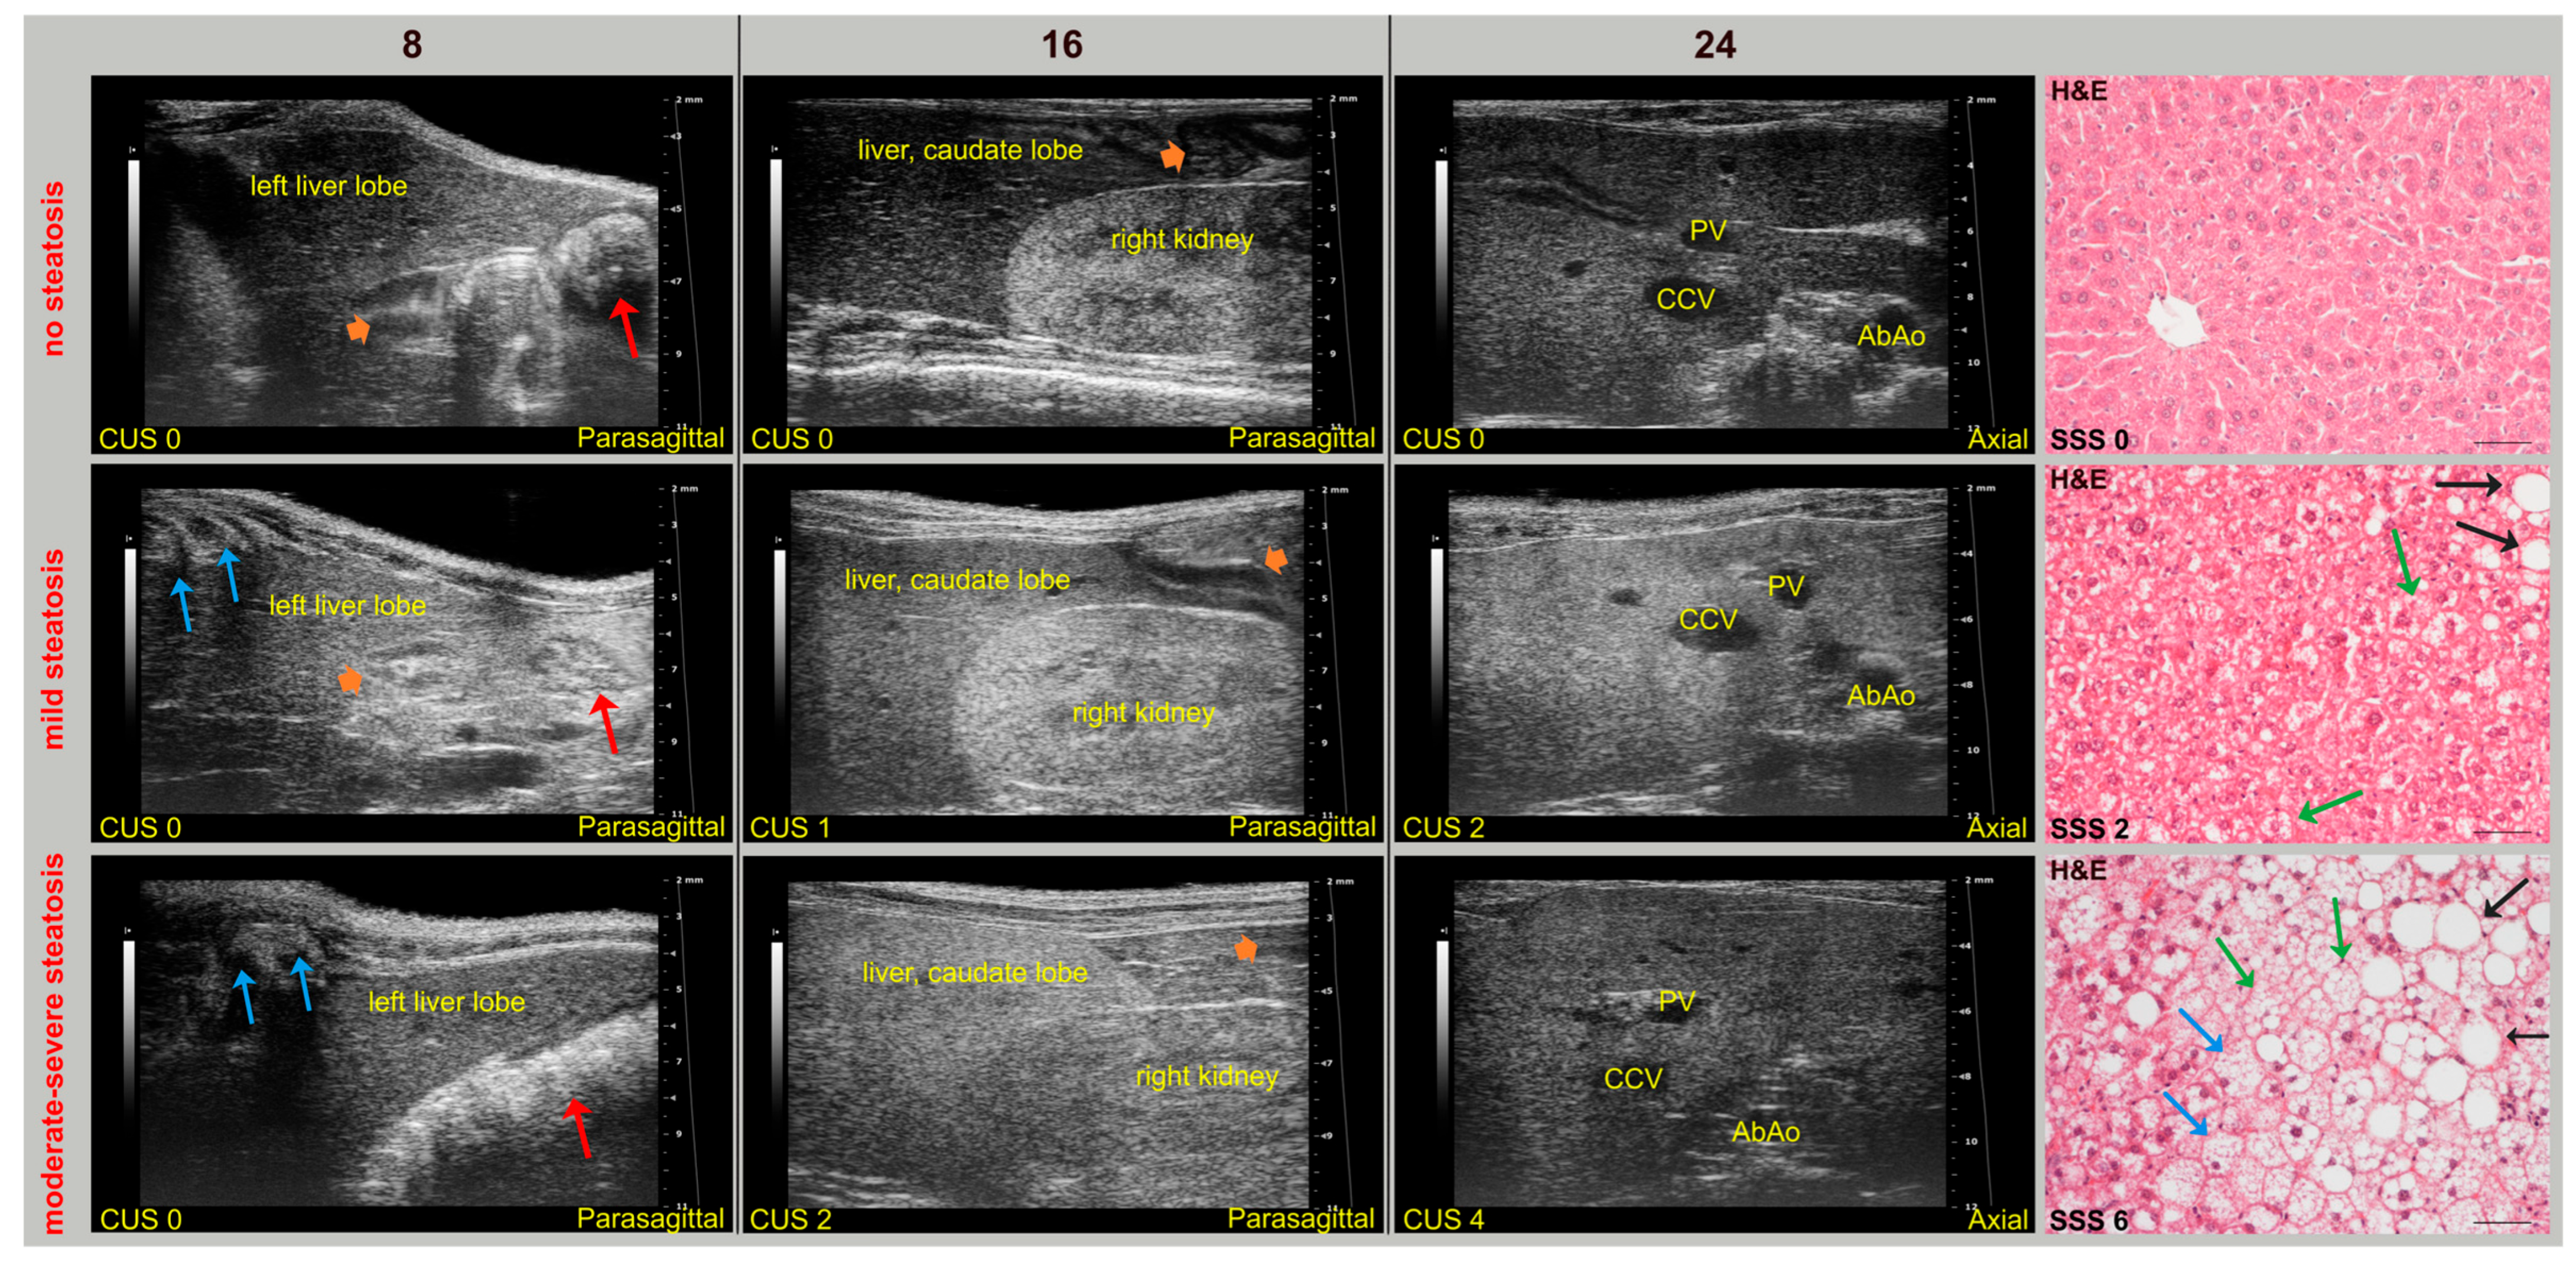

During imaging sessions, body temperature, heart, and breath rates were monitored and normothermia was maintained using a heated platform and an infrared lamp. Mice were anesthetized with inhalant gases (induction chamber: 4% isoflurane plus 2 Lt/min oxygen; maintenance with nose cone: 1.5–1.8% plus 2 Lt/min oxygen). Subsequently, the mice were placed in a supine position and a coupling gel was applied to the trichotomized skin. US two-dimensional (2D) B-mode images of the liver of mice (left, right, and caudate lobes, sagittal and axial planes) at 8 (baseline, pre-diet), 16, and 24 weeks of age were acquired in real time by a veterinary radiologist with 17 years of experience (SG) (

Figure 1). A dedicated HFUS equipment was used (Vevo 2100, FUJIFILM VisualSonics Inc., Toronto, ON, Canada; MS550 transducer: central frequency 40 MHz; focal length 6 mm; depth of penetration 5–15 mm; 30–40 µm axial and 70–90 µm lateral resolution). The time gain compensation and other operating parameters were kept constant throughout experiments (frequency = 40 MHz, frame rate = 16 images/s, gain = 30 dB, depth = 11 mm, width = 13.00 mm, dynamic range = 60 dB, sensitivity = high; transmit power = 100%) to avoid experimental bias. Each liver HFUS acquisition, including overall animal preparation, took no more than 15 min. During recovery, all animals were monitored for any signs of pain or discomfort.

2.4.2. CUS Scoring

B-mode cine-loops were analyzed offline by two experienced veterinary radiologists (S.G., M.G.) who collaborated to reach a consensus on the interpretation of US features. For each mouse, at the chosen time points, HFUS images were selected that represented the best frames in the cine loops for the liver lobes of interest, avoiding motion-related artifacts (in the expiratory and diastolic phases based on the recorded electrocardiogram/respiratory tracings) as well as bone- or intestinal gas-related shadowing. Since histopathological scores are based on evaluation of lipid-droplets accumulation in hepatocytes, we first examined traditional scattering parameters from the echo amplitude histogram of normal and steatotic liver parenchyma. Briefly, the presence and grading of liver steatosis were assessed by visual interpretation of HFUS features, based on protocols validated in both patients and mouse models, expressed using the semiquantitative CUS scoring system: (0) homogeneous liver parenchyma of medium level echogenicity; (1) diffusely increased parenchymal echogenicity; (2) discrete coarsened and heterogeneous parenchymal echogenicity; (3) extensive coarse and heterogeneous parenchymal echogenicity [

15,

16]. Furthermore, the visual appearance of liver echogenicity was rated relative to the renal cortex as (0) lower or (1) equal or (2) higher, as well as the absence (0) or presence (1) of ascites [

18].

2.5. Histological Examination

The liver specimens were collected 1-day after the last HFUS examination to ensure the validity of the histology reference standard, due to the variation in hepatic fat contents over time [

45]. After sacrifice, liver was collected from each mouse and formalin-fixed according to standard procedures. Thereafter, 7 μm sections were cut from each paraffin block and stained with hematoxylin and eosin (H&E) for morphological evaluation. In order to evaluate the relationship between CUS score and histologically determined steatosis, an experienced pathologist (VB) classified the severity of liver steatosis in each mouse based on a validated preclinical scoring system, adapted to histological peculiarities of rodent’s species [

46,

47] from the human NASH–Clinical Research Network scoring system [

48,

49,

50]. Given the different ways of reporting disease scores in the literature, we have provided a detailed description of the specific approach used to measure the hepatic steatosis severity score for each mouse, as recommended [

51].

In particular, steatosis was determined by analyzing the following histological features (5 fields per animal, 200× agnification):

- −

Steatosis: Percentage of the total area occupied by hepatocytes showing microvesicular (multiple lipid droplets inside the hepatocytes) and macrovesicular (a big lipid droplet displacing the nucleus) alterations as 0 (absent); 1 (mild, <10%); 2 (moderate, 10–30%); 3 (severe, >30%).

Hypertrophy: Percentage of the total area occupied by hypertrophic hepatocytes (cellular diameter > 1.5 of a normal hepatocyte) as 0 (absent); 1 (<10%); 2 (10–30%); 3 (>30%).

The final steatosis severity score (SSS) was determined by the sum of the semiquantitative scores for macrovesicular and microvesicular steatosis separately, and hypertrophy. A Nikon Eclipse E600 light microscope equipped with a digital camera and the Nis element v3AR software was used (Nikon Instruments, Melville, NY, USA). For each animal, at least three sections were examined, including distinct liver lobes, avoiding microscopic fields in which hepatic venules and portal tracts were visible.

3.2. Comparison of In Vivo CUS Determinations with Histological Features on Liver Samples

Based on histological criteria examined in the 45 mice studied, predominantly macrovesicular (area%, 4.55 ± 5.54) or microvesicular (area%, 19.01 ± 21.82) steatosis of any extent were observed in approximately 9% and 13% of mice, respectively, whereas a mixed pattern (area%, 36.08 ± 24.17) of small and large lipid droplets of any extent was seen in 78% of mice, including hypertrophic hepatocytes in 31% of mice. HFUS changes suggestive of hepatic steatosis were observed in 36 (80%) mice.

Overall, SD-fed mice had a homogeneous and isoechoic liver parenchyma throughout the study, whereas the liver parenchyma of WD-fed mice tended to become progressively hyperechoic and heterogeneous, with hepatic echogenicity equal to or greater than that of the renal cortex. No mice showed ascites. In addition, mild inflammation and fibrosis were observed in the liver of WD-fed mice (62.5% and 25% of WT mice, 87% and 80% KO mice, respectively). Interestingly, a WT mouse and a KO mouse fed SD showed mild sonographic parenchymal heterogeneity, although histological features of steatosis were absent. Nevertheless, evident glycogen content in hepatocytes or mild fibrosis, with different distribution in liver lobes, were observed in these mice by Periodic acid–Schiff staining and Masson’s trichrome, respectively. Similar findings were also found in four WT WD-fed mice (False Positive Rate, FPR = 0.4). These specificity issues could be explained by considering that fat, glycogen, and fibrotic tissue can cause increased HFUS scattering, producing similar sonographic changes in liver alterations other than steatosis [

62,

63]. Indeed, mild-to-moderate hepatic steatosis was confirmed by histology in three SD-fed KO mice (43%), which exhibited corresponding changes in US features over time. In particular, histology-confirmed US findings of steatosis started to appear at 16 weeks of age in both WT (62.5%) and KO (100%) mice fed WD, with overall higher severity in KO mice. Additionally, HFUS images were examined to detect renal abnormalities. In agreement with biochemical tests, no mouse showed an abnormal US renal appearance, with clear visualization of the corticomedullary border, renal papilla, and echogenic renal capsule. Representative HFUS liver views and related histological images are provided in

Figure 4.